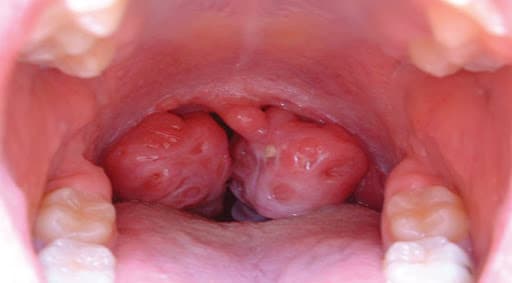

– Những hốc mủ trắng. Amidan thường sẽ sưng to, đỏ và có những vùng trắng gọi là hốc mủ. Các hốc mủ không chỉ xuất hiện trên bề mặt amidan mà còn xuất hiện xung quanh amidan tạo nên những màng trắng bao quanh.

Hình ảnh viêm amidan bắt đầu xuất hiện các hốc mủ trắng